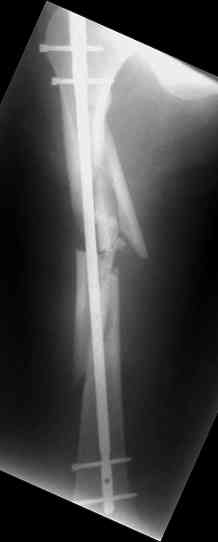

Надеюсь сейчас показать перелом, а потом синтез.